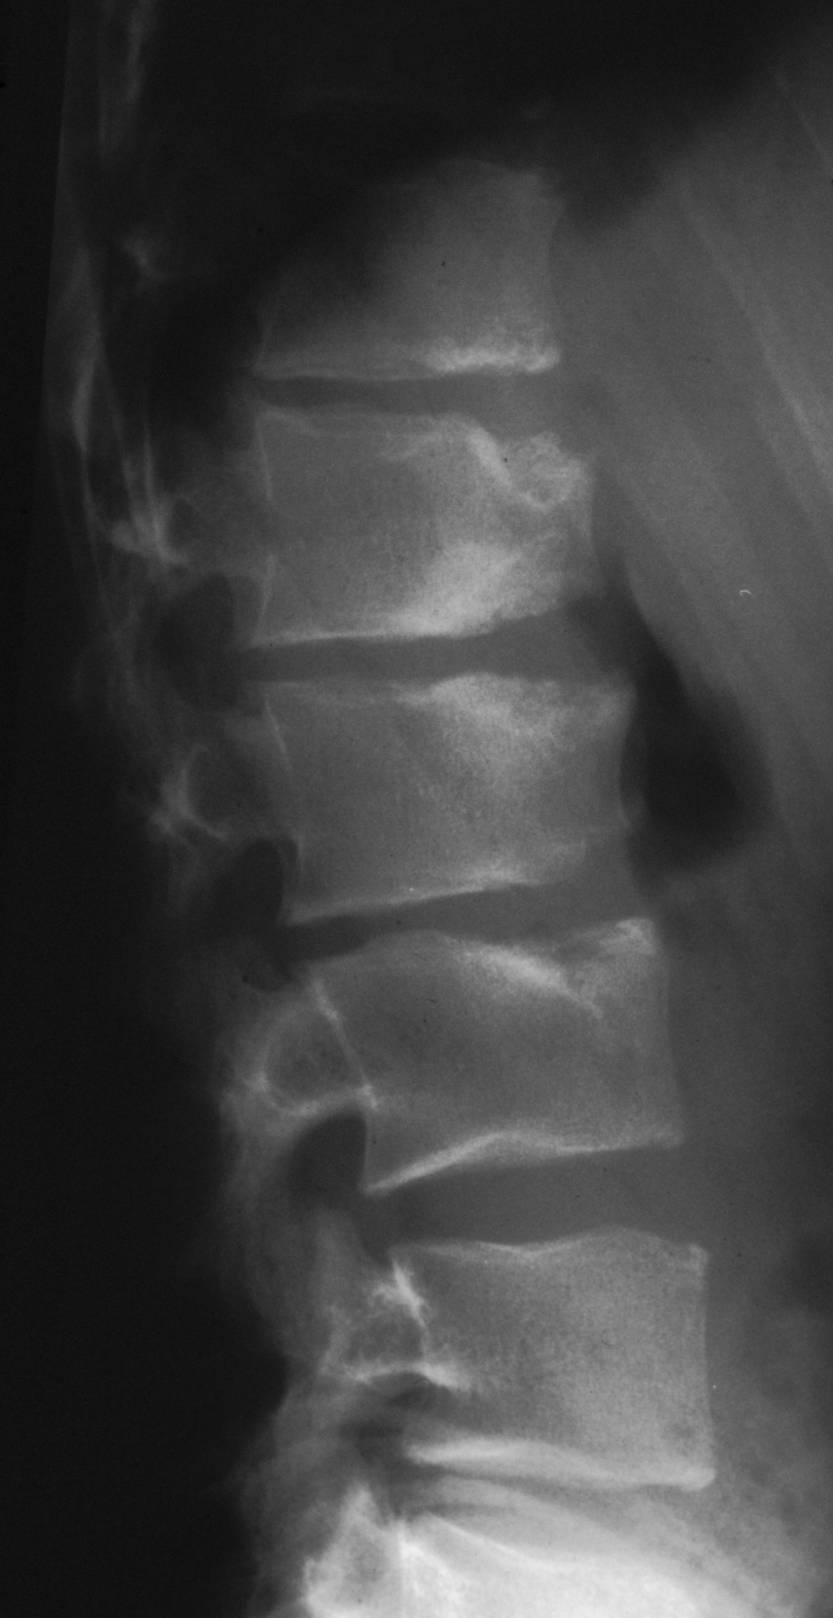

Beweisend ist die radiologische Untersuchung des betreffenden Wirbelsäulenabschnitts im seitlichen Strahlengang (Abb. 1). Typische ist die unruhige und wellige Struktur der vorderen Deckplattenanteile, an denen sich rundliche Aufhellungszonen (Schmorl-Knötchen) zeigen können. Mitunter ist die den intraossären Bandscheibenhernien gegenüberliegende Region der Grundplatte vorgewölbt und sklerosiert (Endgren-Zeichen). Bei längerem Verlauf sind die Wirbelkörper keilförmig deformiert, wobei deren dorsoventraler Durchmesser vergrößert sein kann. Die Diagnose des Morbus Scheuermann sollte erst gestellt werden, wenn mindestens drei Wirbelkörper die typischen röntgenologischen Zeichen aufweisen und die Keilform jedes Wirbelkörpers mindestens 5° beträgt. Die Kyphose der Brustwirbelsäule beträgt mehr als 45°, wobei der Scheitel im Bereich des siebten bis neunten Brustwirbelkörpers liegt. Betrifft die Erkrankung mehr den thorakolumbalen Wirbelsäulenabschnitt, liegt der Scheitel der Deformität in Höhe des zehnten bis zwölften Brustwirbelkörpers.

Abb. 1.

Radiologische Darstellung der Wirbelsäule im seitlichen Strahlengang mit vorderem Kantenabbruch, intraspongiöser Diskushernie (Schmorl-Knötchen) und verschmälertem Intervertebralraum